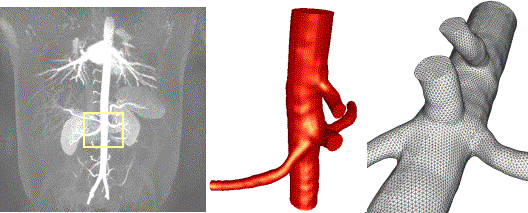

3.2. Renal Arteries

Tubular deformable models were used to reconstruct a portion

of the abdominal aorta in the region of the renal arteries

from contrast-enhanced MRA images (Fig. 4a). A deformable

model was used for each branch and later all the branches

were merged using the adaptive voxelization method. The

watertight model thus created (Fig. 4b) was then used to

generate a finite element grid with a uniform element size

distribution (Fig. 4c).

a)

b)

c)

Figure 4. Generation

of a finite element grid of the renal arteries from contrast-enhanced

MRA images: a) MIP of the anatomical images; b) reconstructed

model; c) finite element mesh.